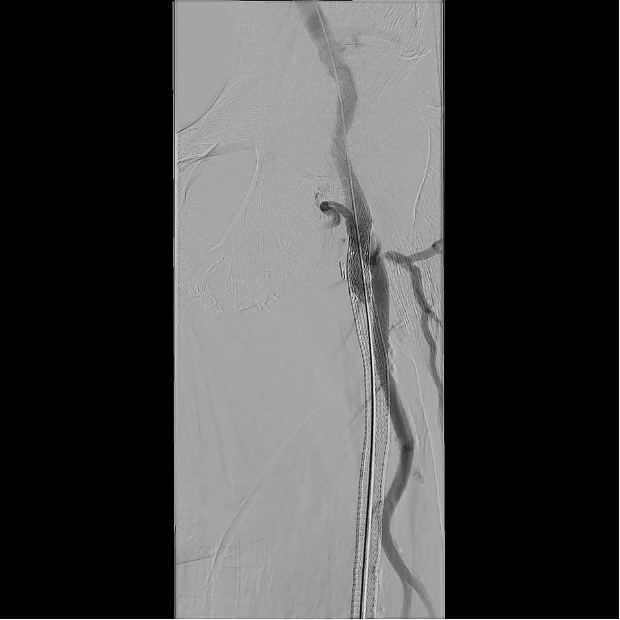

Based on his comorbidities, history of recurrent stenting of the left SFA, and an occlusion of the SFA over 200 cm, he was deemed to be an appropriate candidate for percutaneous transmural arterial bypass (PTAB). However, in order to establish long-term patency, we proceeded to gain posterior tibial artery access to identify a 3-vessel runoff (Figure 2). With this information, using the outline of the stents in left SFA and using a 0.018-in Glidewire Advantage (Terumo) and a 0.018-in Rubicon catheter (Boston Scientific), we were able to obtain access into the left profunda femoral artery (Figure 3). Despite multiple-balloon angioplasty, the recoil within the left common femoral artery (CFA) left little option but to place a 7.0-mm Eluvia stent (Boston Scientific), which was overlapped with the proximal stent in the left SFA (the profunda femoral artery was patent after balloon angioplasty; Figure 4).

After gaining access into the SFA, the first step of crossing from the SFA into the femoral vein was done with the Endocross catheter (Endologix; Figure 5). Although it had to be done through stent struts, this proved to be fairly easily accomplished with minimal resistance. A 0.014-in Grand Slam wire (Asahi Intecc Medical) was snared from the Endocross to the femoral vein using a pre-existing snare. The crossover site was then dilated using a 5.0-mm Serranator balloon (Cagent Vascular; Figure 6), allowing for the Endocross to advance into the distal femoral vein for distal access into the P1 portion of the popliteal artery through a pre-existing Supera stent (Abbott Cardiovascular) with minimal resistance. This was pre-dilated with a 4.0-mm Coyote balloon (Boston Scientific) followed by a 5.0-mm Serranator balloon (Figure 7). After sufficient pre-dilatation, the Torus stents (Endologix) were placed from the distal anastomosis to proximal anastomosis (5.5 mm distally and 6.5 mm proximally; Figure 8) followed by post-dilatation with a 6.0-mm Mustang balloon (Boston Scientific; Figure 9). Repeat angiographic assessment showed good apposition and expansion of the stents and robust vessel runoff down to the foot (Figure 10). The patient’s wound did require transmetatarsal amputation but was spared an above-knee amputation. His wounds had shown sufficient healing 3 months from the principal procedure.